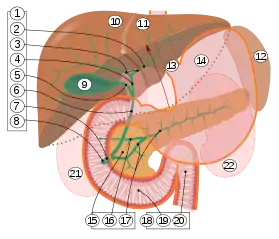

1. Bile ducts: 2. Intrahepatic bile ducts, 3. Left and right hepatic ducts, 4. Common hepatic duct, 5. Cystic duct, 6. Common bile duct, 7. Ampulla of Vater, 8. Major duodenal papilla

9. Gallbladder.

10–11. Right and left lobes of liver.

12. Spleen.

13. Esophagus.

14. Stomach.

15. Pancreas: 16. Accessory pancreatic duct, 17. Pancreatic duct.

18. Small intestine: 19. Duodenum, 20. Jejunum

21–22. Right and left kidneys.

The front border of the liver has been lifted up (brown arrow).[1]